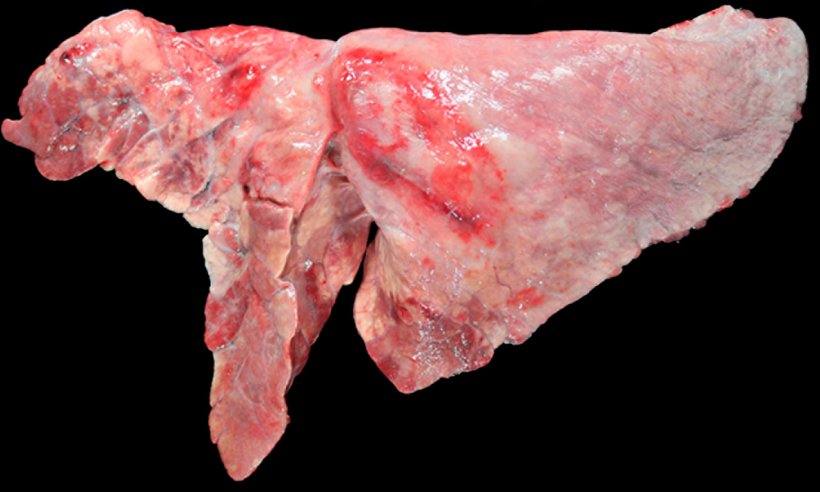

Bei Tieren mit Koinfektionen von M. hyopneumoniae und SIV (Abb. 4) wurden im Falle einer Infektion von Schweinen mit M. hyopneumoniae, die sich danach mit einem niedrigvirulenten Stamm des Schweineinfluenzavirus infizierten, eine starke Zunahme der klinischen Symptome und Lungenläsionen beobachtet, was darauf hindeutet, dass Mykoplasmen die Virulenz dieser SIV-Stämme erhöhen können.

Abbildung 4: Mit M. hyopneumoniae und SIV koinfizierte Lunge eines Schweins. Rote konsolidierte Stellen in den kranioventralen Teilen der Lunge und einige kleinere Bereiche im Zwerchfelllappen. Bei diesen kranioventralen Läsionen gibt es sowohl Läsionen durch M. hyopneumoniae als auch Läsionen aufgrund von SIV, so dass eine makroskopische Unterscheidung zwischen ihnen unmöglich ist.